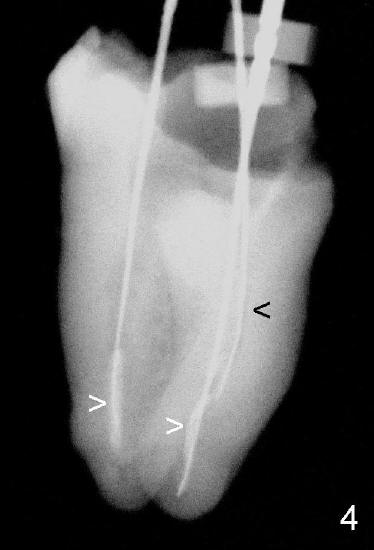

The void in the mesial root turns out to be a missing mesiobuccal canal (Fig.4,5 black <). Initially, RCT filling material is difficult to remove from apical portion of the distal and mesiolingual canals (Fig.4 white >), while the apical portion of the mesiobuccal canal is obliterated.